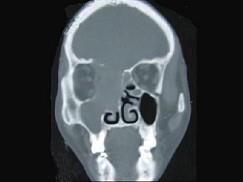

女性,53岁,右侧鼻腔流血近一年,近来头痛,行CT检查如图所示,请选择正确的答案 ( )

• A.鼻腔内血管瘤

• B.鼻腔内息肉

• C.鼻腔癌

• D.鼻腔炎性假瘤

• E.副鼻窦炎

答案: C